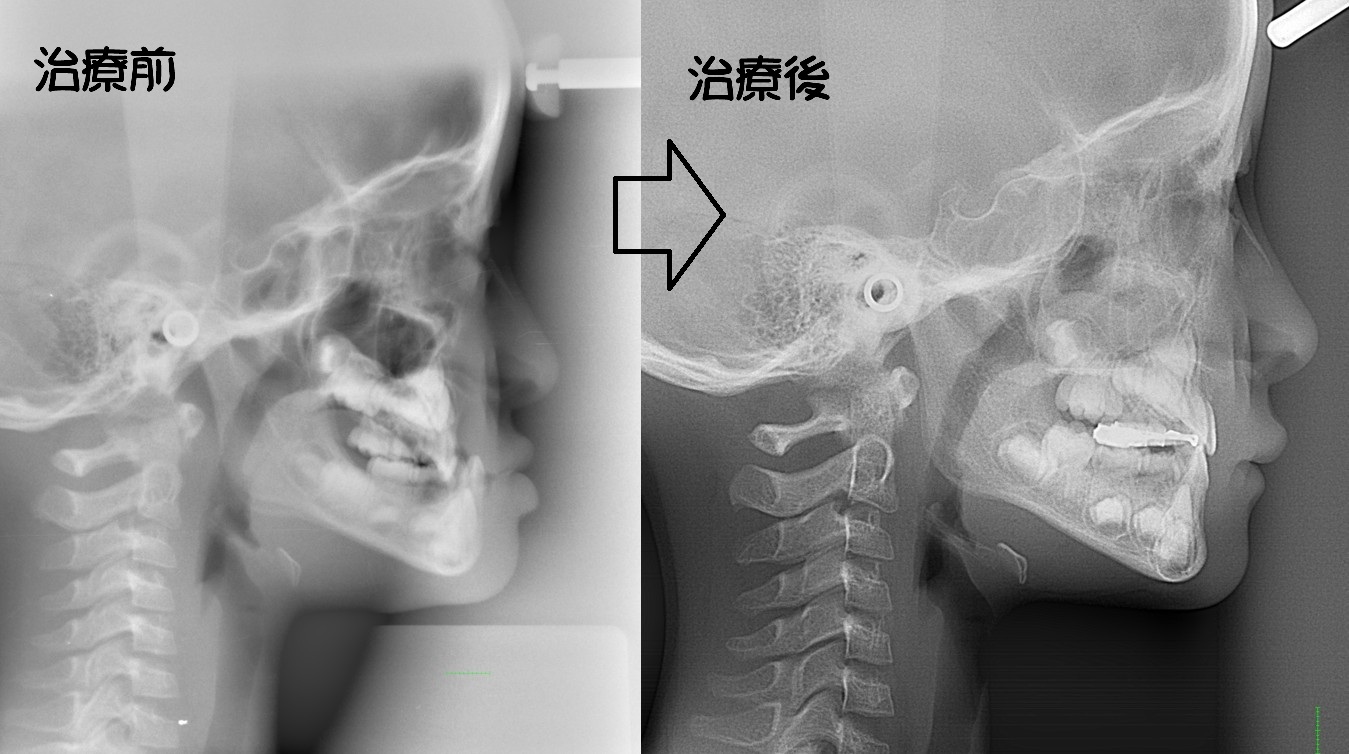

顎変形症

骨格性反対咬合・骨格性上顎前突・骨格性開咬・骨格性下顎側方偏位 などの外科矯正手術を必要とするもの

外見の改善を重要視するならば、矯正治療と外科処置を併用することにより適切な噛み合わせを回復したほうがよい場合もあります。

・主訴:下あごが出ている

・診断:骨格性下顎前突

・年齢:27歳

・使用した主な装置:マルチブラケット装置

・抜歯部位:なし

・治療期間:30か月

・通院回数:36回

・費用の目安:保険適応。保険矯正代金は、20万円くらい。症状・期間によってかわります。

・その他大学病院で外科矯正手術代金がかかります。

リスク・副作用:

・骨の移動(外科矯正手術)を行うために入院期間:約2週間・手術代金別途かかります。

・虫歯にならない様に、通常の歯磨きを工夫することが必要です。

・歯が動く際に、歯のゆれを痛みとして感じることがあります。

・根の吸収が起きることがあります。

・保定をしないと後戻りが起きることがあります。